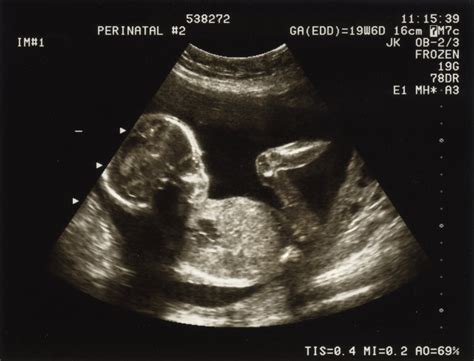

1. Confirmarea și monitorizarea sarcinii prin ecografie

Prima ecografie, recomandată la o săptămână de întârziere a menstruației, are rolul de a confirma sarcina. În această etapă, dozarea β-HCG ar trebui să depășească 1000 UI, iar sarcina să fie vizibilă ecografic.

Ecografia transvaginală vs. transabdominală

Ecografia transvaginală permite obținerea primelor imagini ale sacului ovular intrauterin la valori β-HCG de minim 500 UI (aproximativ 5 săptămâni). În cazul sarcinii extrauterine, vizualizarea este posibilă la valori β-HCG ce depășesc 1500 UI. Ecografia transabdominală poate vizualiza sacul ovular dacă acesta are un diametru de cel puțin 5 mm (6-7 săptămâni).

Evaluarea viabilității sarcinii

Viabilitatea sarcinii se evaluează prin ecografii de control, monitorizând:

- Creșterea dimensiunilor sacului gestațional.

- Apariția veziculei viteline - o structură inelară cu rol nutritiv pentru embrion. Dimensiunile optime sunt între 3-5 mm; valori sub 2 mm sau peste 6 mm pot indica un prognostic rezervat.

- Apariția și creșterea dimensiunilor embrionului. Lungimea cranio-caudală (LCC sau CRL) este cel mai fidel indicator pentru stabilirea vârstei gestaționale și a datei probabile a nașterii, cu o eroare de +/- 3 zile în primul trimestru, crescând spre termen.

- Apariția și evoluția bătăilor cordului fetal (BCF). Activitatea cardiacă devine vizibilă în jurul săptămânii a 6-a, cu o frecvență de 100-110 bătăi/minut, ajungând la 170-180 bătăi/minut la 9-10 săptămâni, apoi stabilizându-se la 140-160 bătăi/minut până la termen.